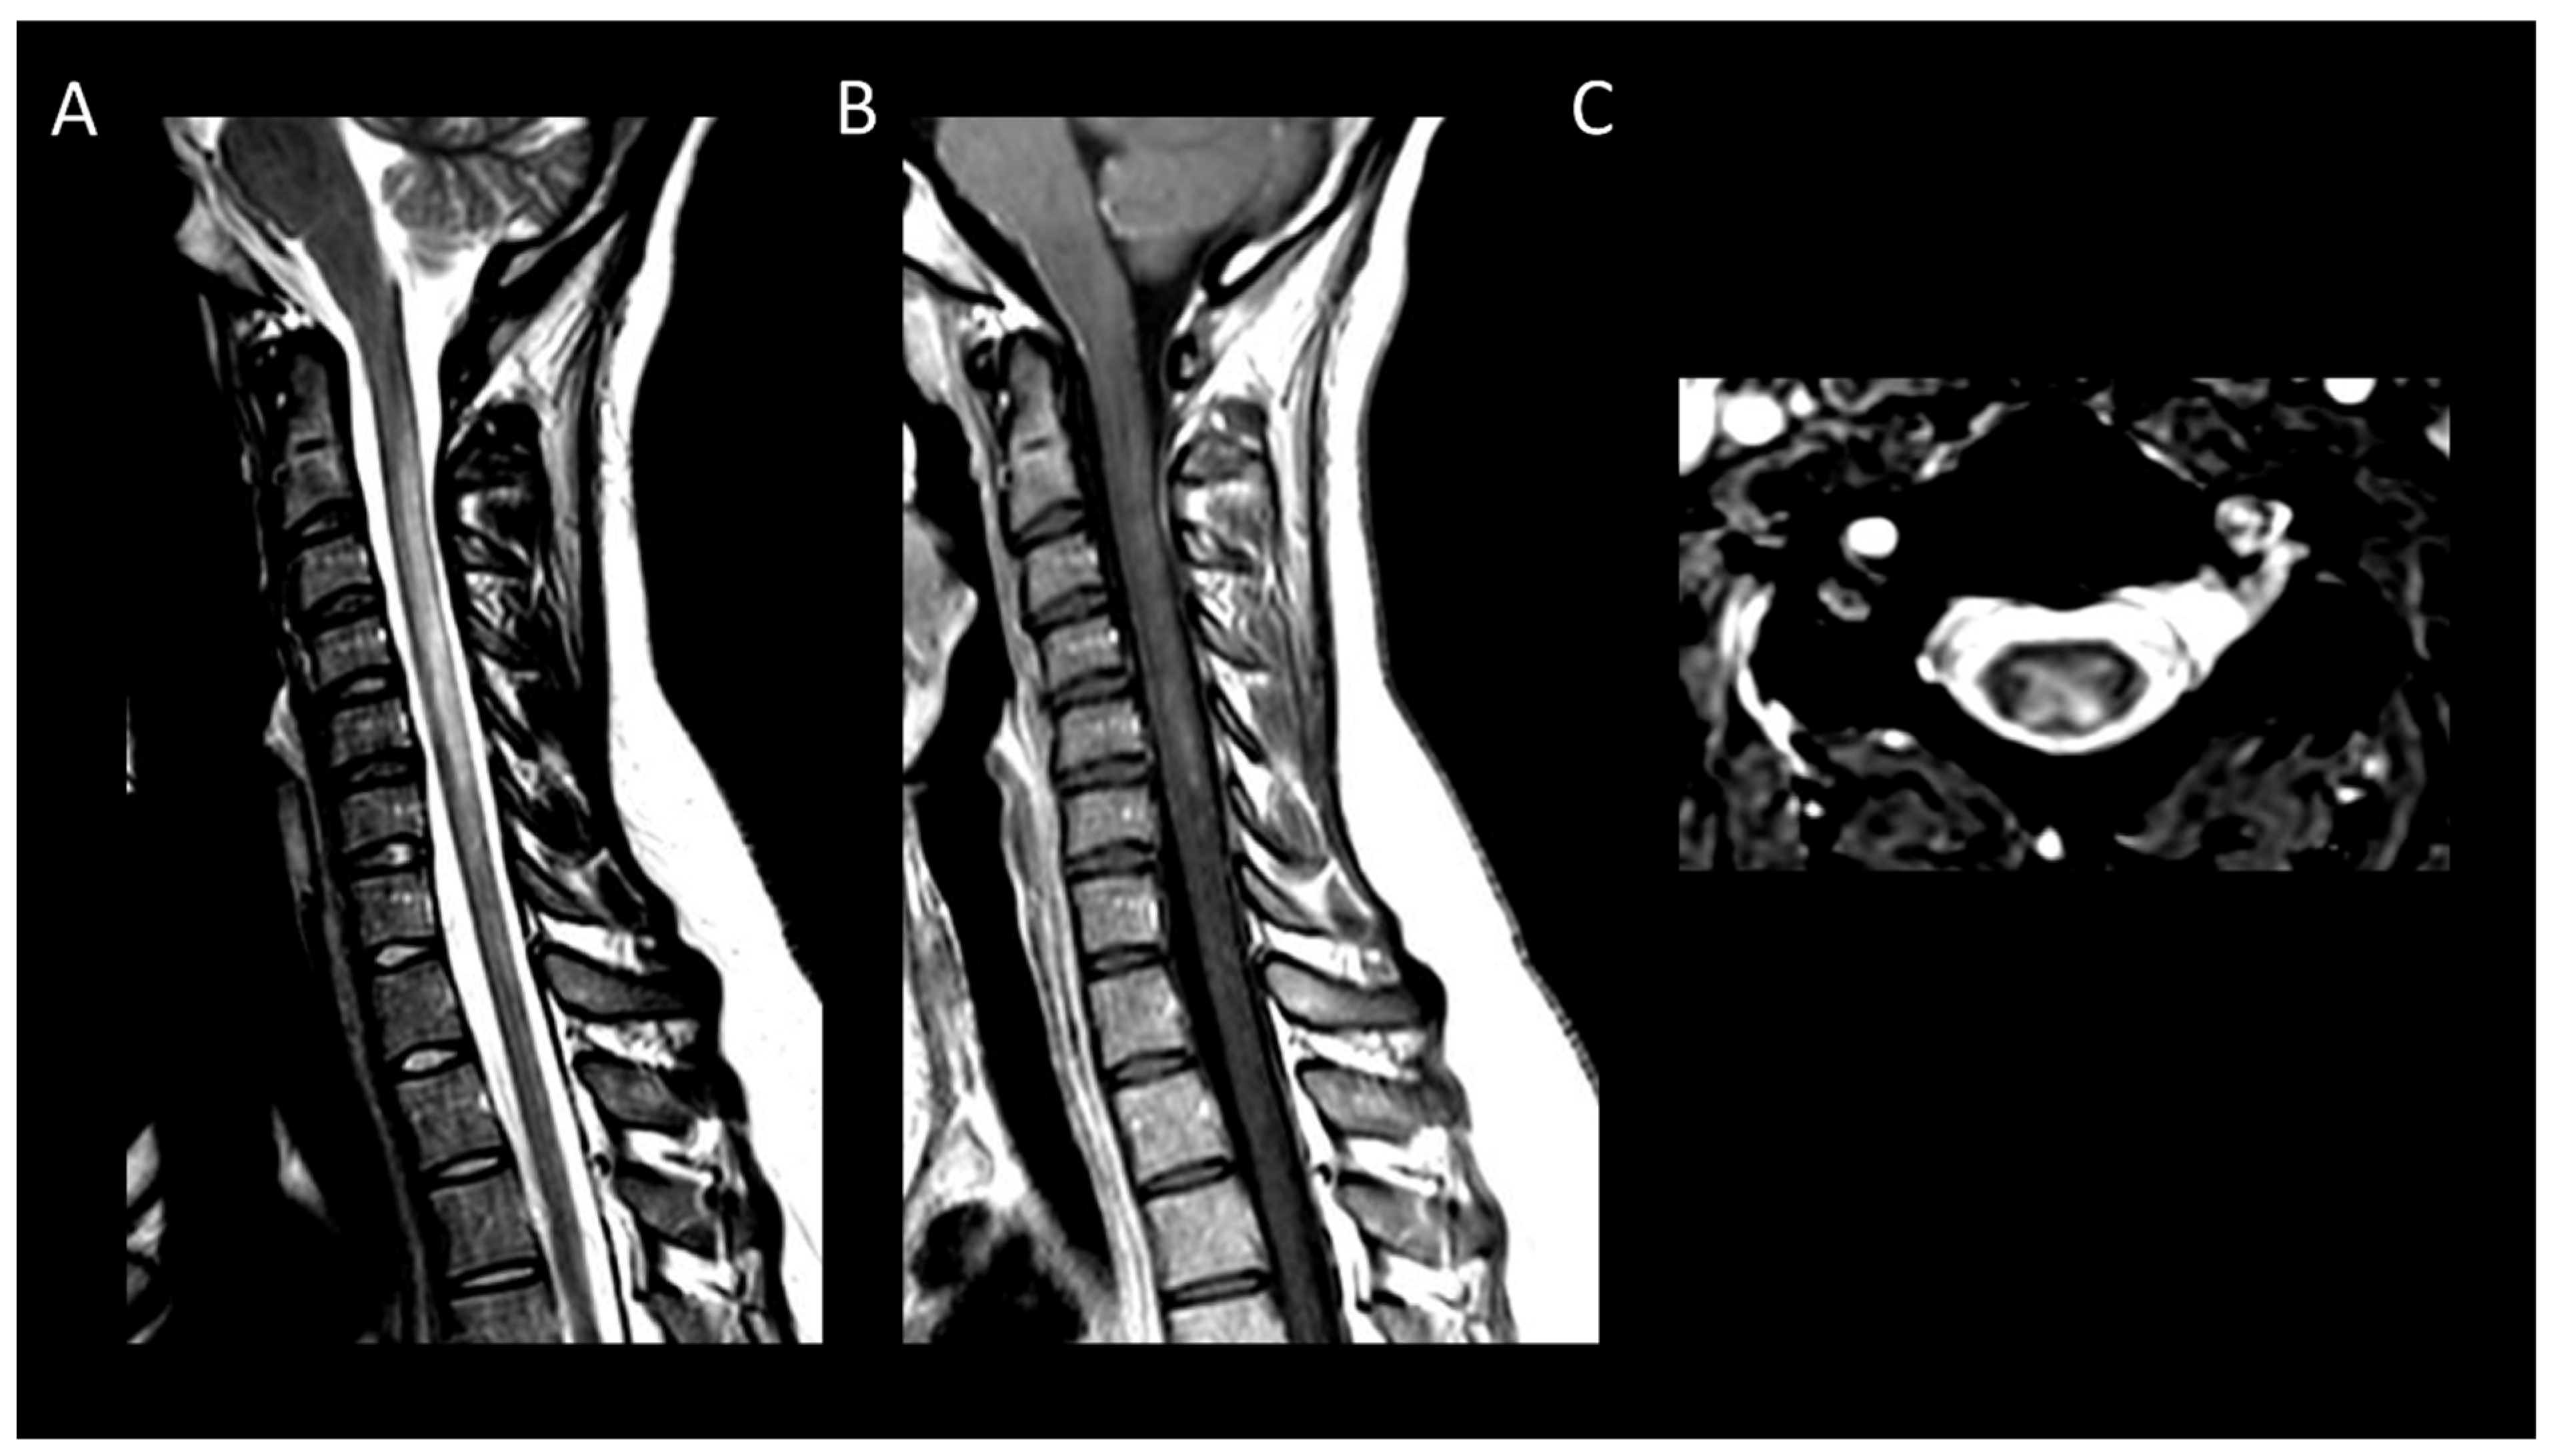

3.2. Degenerative Compressive Myelopathy

3.3. Vascular Myelopathies

3.3.1. Spinal Cord Infarction

- Flanagan, E.P.; Krecke, K.N.; Marsh, R.W.; Giannini, C.; Keegan, B.M.; Weinshenker, B.G. Specific Pattern of Gadolinium Enhancement in Spondylotic Myelopathy. Ann. Neurol. 2014, 76, 54–65. [Google Scholar] [CrossRef]

- Syc-Mazurek, S.B.; Montenegro, M.; Clarke, M.J.; Flanagan, E.P. MRI with Neck Extension to Diagnose Cervical Spondylotic Myelopathy. Pract. Neurol. 2022, 22, 162–163. [Google Scholar] [CrossRef] [PubMed]